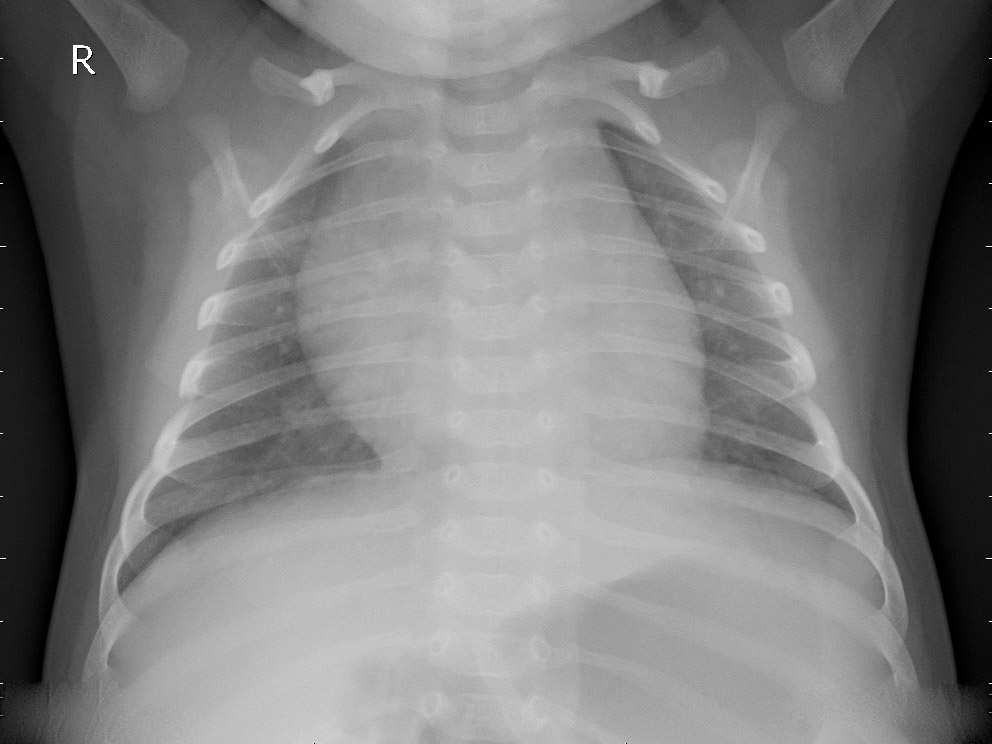

This dataset comprises 5,856 CXR images, divided into three categories: Normal, Bacterial Pneumonia, and Viral Pneumonia. For the purpose of this study, we frame the problem as a two-class classification task distinguishing between a healthy person (Normal) and one having any type of pneumonia (Pneumonia). This choice aligns with previous studies in this field [singh2023pneumonia, ayan2022diagnosis, szepesi2022detection]. The sample images from each class are shown in Figure 2.